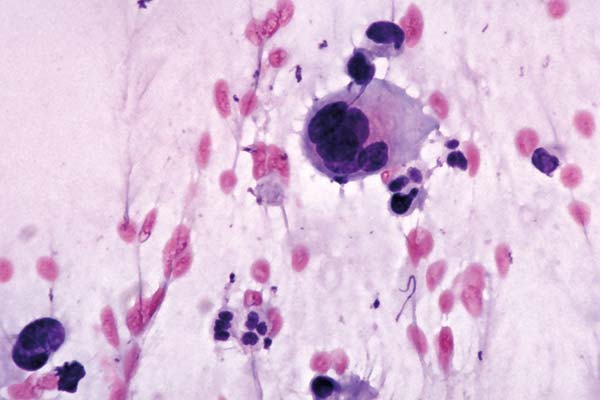

richtige Antwort:

d. Histiozytäre Riesenzelle

- man findet sie häufig bei Entzündungen und nach operativen Eingriffen

- polymorphes Erscheinungsbild mit häufig vakuolisiertem Zytoplasma

- gleichmäßige Form und Größe der Zellkerne